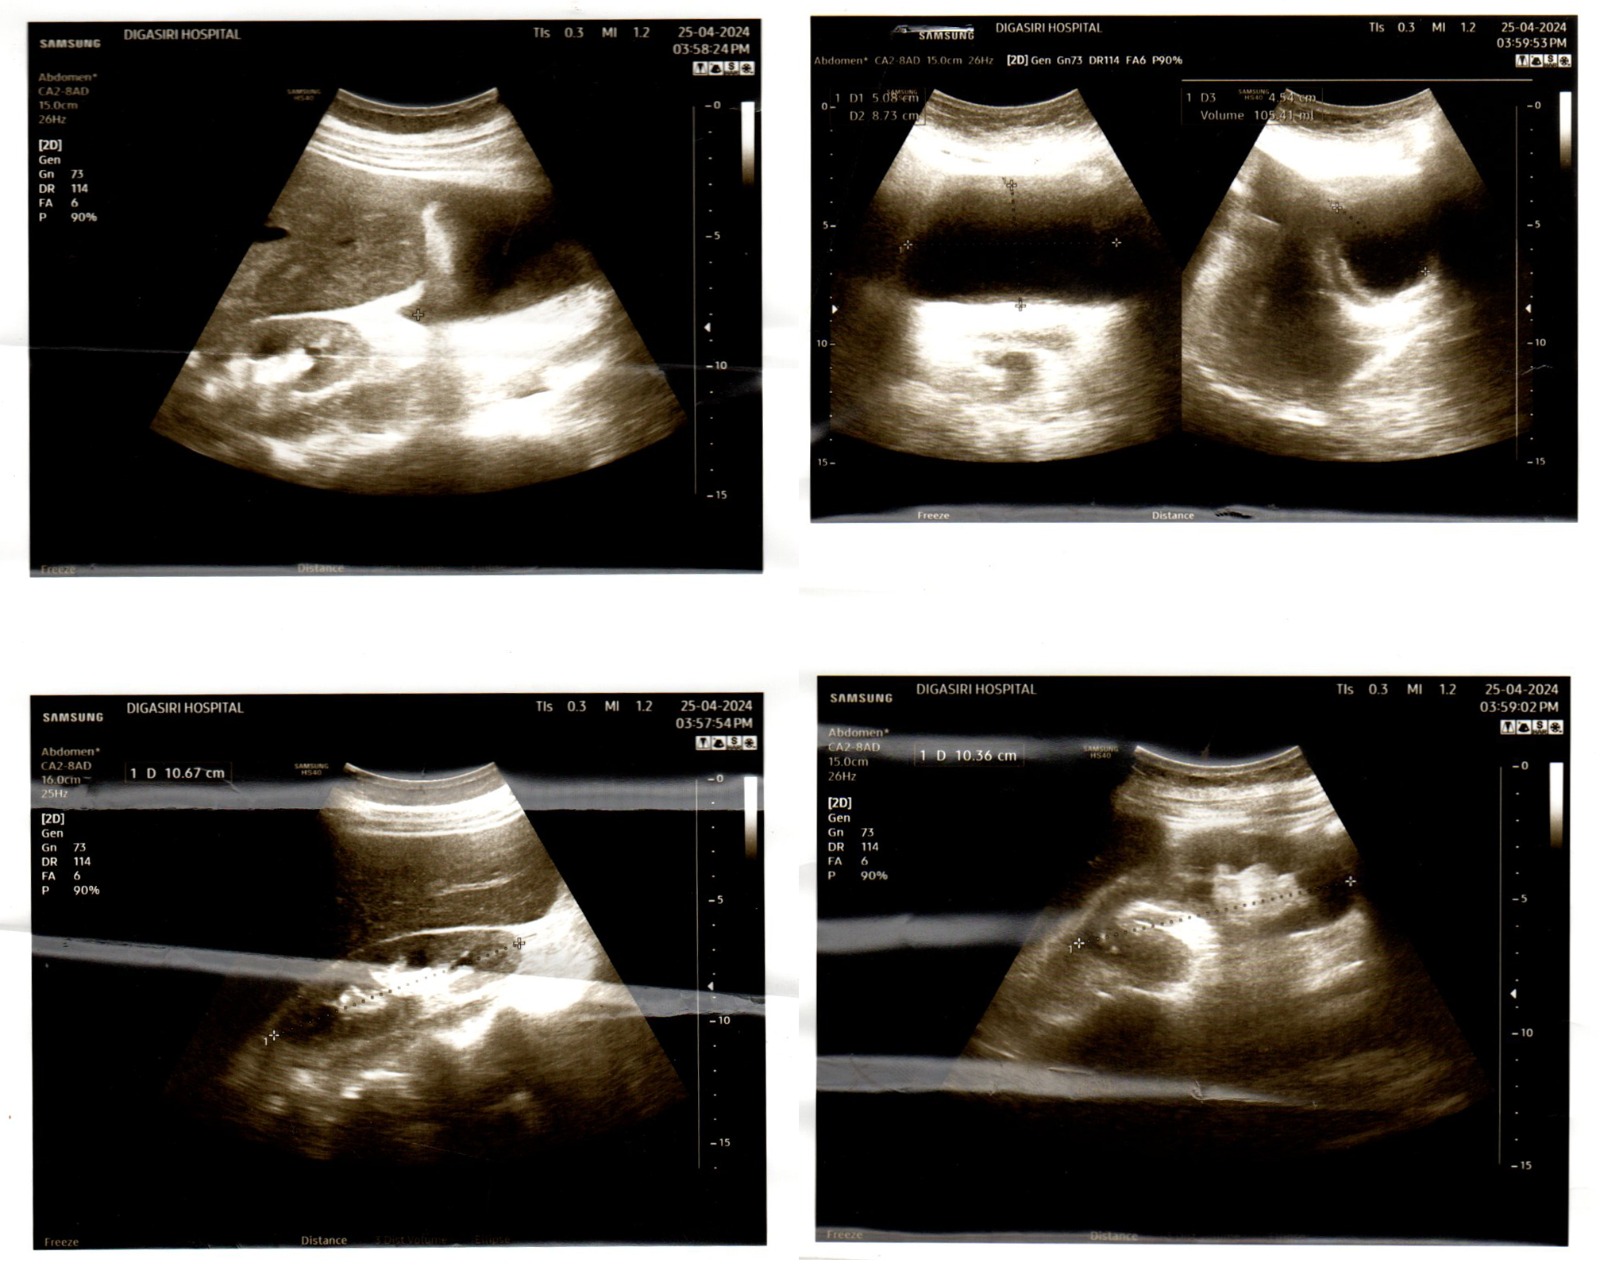

மதுரங்குளி - கனமூலை ஸாஹுல் ஹமீது ஜும்ஆ மஸ்ஜித் மஹல்லாவை சேர்ந்த பாத்திமா ஸஹானா அவர்கள் இரண்டு சிறுநீரக நோயினால் பாதிக்கப்பட்டு சிகிச்சை செய்வதற்காக பாரியதொரு பணத்தொகையை (95 இலட்சம்) தேவைப்படுகிறது